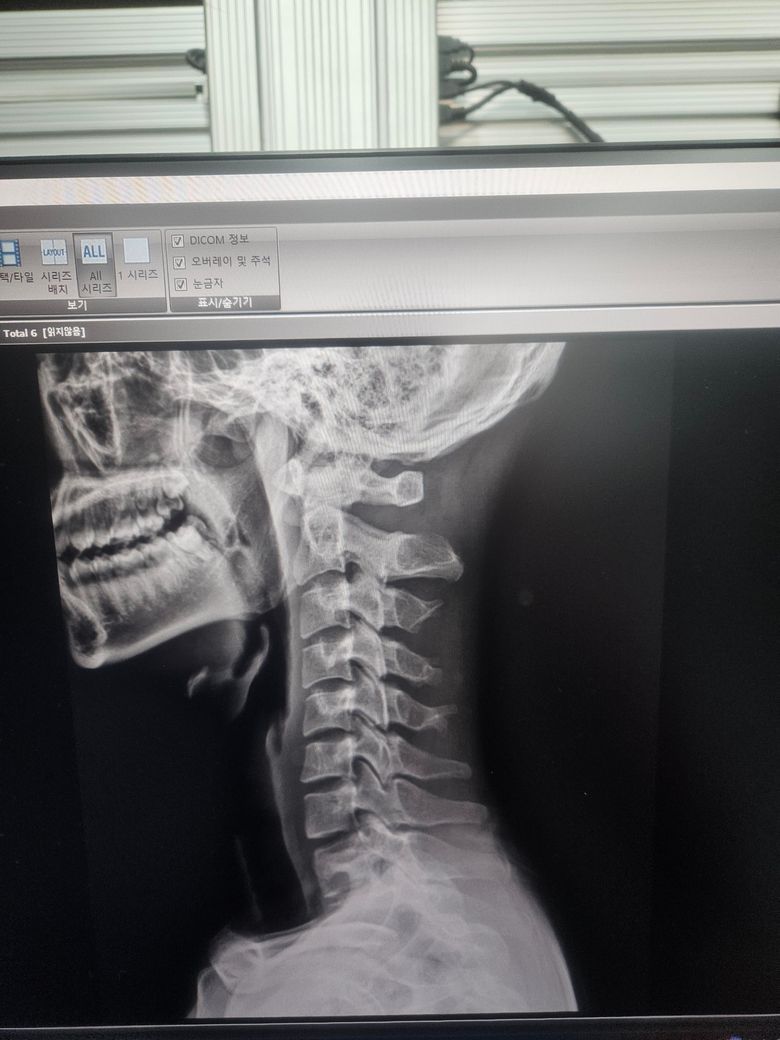

경추 불안정증인가요? 아시는분 제발 ㅜㅜ

몇번째 글 올리는건지 모르겠네요 경추 1번 과 2번 사이가 3mm미만이면 정상범위라는데 저는 몇미리인가요 불안정증이 있는건가요 ㅜㅜ

• 2번 째 사진

실제 영상을 보면서 측정을 해야 합니다

사진을 찍은 것으로는 측정이 되지 않습니다.

단순히 영상 사진을 다시 사진으로 찍은 자료만으론 판단 불가합니다. 세팅을 어떻게 했느냐에 따라 보이는 길이와 실제 길이가 차이가 나기 때문이죠. 사진을 다시 사진으로 찍으면서 생기는 오류도 있을수 있구요.

영상 찍은 병원 담당 의사에게 물어보는게 제일 정확합니다